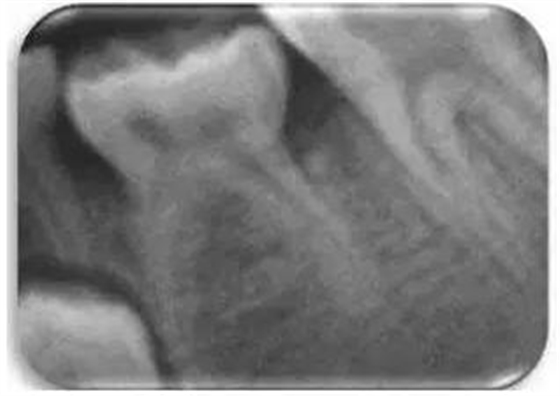

發(fā)育不全被定義為乳磨牙分叉下方的骨嵴沒有鈣化的跡象。采用Demirjian方法將相應(yīng)的前磨牙發(fā)育分為8個(gè)階段。對應(yīng)牙齒發(fā)育缺失的“0期”已被作者另外考慮(圖2)。

圖2 影像學(xué)觀察到的由左側(cè)第二乳磨牙的低牙合導(dǎo)致的前磨牙發(fā)育不全。